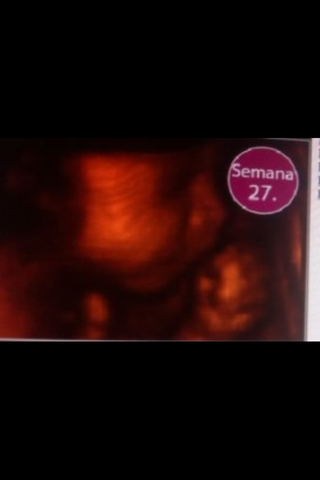

Él bebe ya tiene pestañas

Sus medidas son de 22 cm y su peso alrededor de 1k

Desarrolla el reflejo labial de succión

Sus medidas son de 23 cm y su peso de 1k

Ya se escuchan los latidos del bebe

Los pulmones se vamn formando, ya que son los últimos en formar